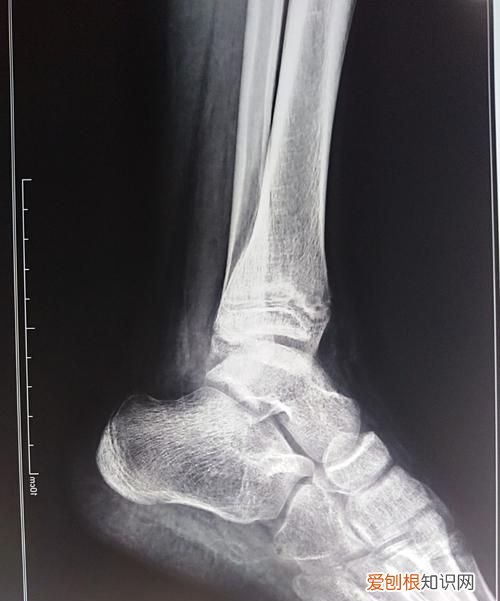

正如之前所说,随着骨折愈合,骨折端会形成新骨头,因此,判断骨折愈合情况最重要的方法就是拍片观察骨折端,可以是X光,也可以是CT 。一般而言,普通的X光片就足够了 。在骨折愈合第二阶段,也就是骨折后3-4个月时,愈合良好的骨折端可以看见云雾状的白色阴影,也就是医学上的“骨痂”,看见骨痂出现,就说明骨折长得不错 。除此之外,还有很多办法可以判断骨折愈合情况,比如骨折处肿胀消失,局部没有疼痛,按着也不疼,肢体可以自由活动,甚至可以行走或者拿些东西,这些都是骨折好转的表现 。

【X光片如何看骨痂,怎样才能知道骨折好了】以上就是关于X光片如何看骨痂,怎样才能知道骨折好了的全部内容,以及X光片如何看骨痂的相关内容,希望能够帮到您 。